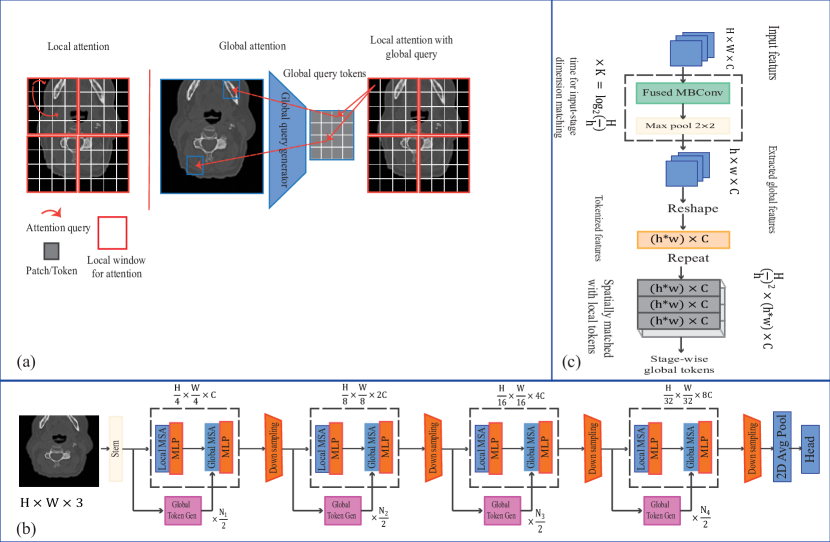

The Global Context Vision Transformer (GCViT) presents a pioneering vision transformer architecture aimed at optimizing parameter and computational efficiency by simultaneously accounting for local and global spatial interactions within images. GCViT adopts a hierarchical structure characterized by the alternation of local and global self-attention modules as depicted in Figure 2.

In its design, GCViT integrates local self-attention to capture short-range dependencies within defined local windows, a concept akin to prior models such as the Swin Transformer. However, the defining innovation in GCViT is the introduction of global query tokens. These tokens are generated from the entire image through a CNN-like module, and they interact with local key and value tokens within each window.

This pioneering approach empowers the global self-attention mechanism to effectively capture long-range dependencies spanning across these windows. Remarkably, this is achieved without the need for computationally expensive operations like shifting windows. Furthermore, GCViT employs a modified convolution block for downsampling, which significantly enhances the modeling of inter-channel dependencies within the network. This distinctive architecture holds immense promise for applications like vertebral classification, offering a powerful blend of local and global information capture efficiently and effectively [30].

This section outlines the methodology employed for cervical vertebrae classification in the current study. To achieve this objective, a multi-input deep neural network is leveraged for vertebrae classification. This network accommodates two types of inputs: images and metadata, both of which contain essential features such as image positions and slice ratios. Given the sequential nature of image acquisition in CT imaging, the inclusion of these metadata features proves particularly advantageous. The network architecture integrates the Global Context Vision Transformer, with pre-trained weights, to handle the image input, while the metadata input undergoes processing through three fully connected layers. Subsequently, the extracted features from both inputs are concatenated, and two additional fully connected layers are employed for the final classification. The schematic of the network is presented in Figure 5